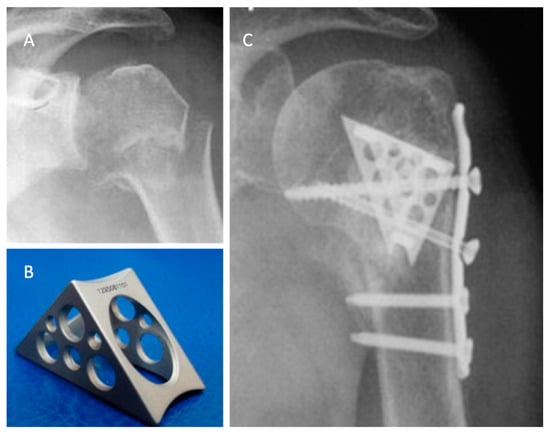

The Da Vinci system or triangular block bridge is a titanium triangle-shaped open prism, whose opposite faces are pierced and jointed with three pegs, one for each vertex (Figure 3). The triangle shape represents the evolution of the triangle-shaped bone block, which is originally handcrafted from an allograft such as iliac crest bone. The shape evolved from the beginning to the definitive version of the titanium cage (produced by Lima, San Daniele del Friuli, Italy, up to 2008 and then by Arthrex, Naples, FL, USA) [29]. Because five different sizes are available, the choice of the correct size and the exact position are therefore important. Each vertex has to fit into the head, the greater tuberosity, and the shaft, with the hypotenuse turned towards the metaphysis. This positioning ensures medial support, stopping the head from sliding down and ensuring adequate fracture support. It acts both as an expander and a metallic bridge on which it is possible to reconstruct all the fragments using minimal osteosynthesis with k-wires, cannulated screws, and trans-osseous sutures. The device aims to increase the stability in fracture with metaphyseal bone loss and to increase the proximal humeral re-vascularization and healing. That is due to stable effect obtained with the association of medial support and lateral fixation.

Figure 3. The use of a metallic cage for a proximal humeral fracture associated to plate fixation: (A) pre-operative X-ray of a displaced four-part humeral fracture-dislocation in a right shoulder; (B) The Da Vinci cage; (C) post-operative X-ray. Credit: Figure 3 from Russo et al. [40], permission conveyed through Copyright Clearance Center, Inc. (Order license ID 1027717-1).

Russo et al. retrospectively evaluated a total of 71 patients with two-, three-, and four-part proximal humerus fractures in three different case series. In 2013, they published the results of a retrospective evaluation of 69 proximal humeral fractures treated with the Da Vinci System between 2005 and 2010 [40]. In all cases, a deltopectoral approach was performed. The titanium cage was used to fill the void of the metaphysis. The fixation was performed with minimal osteosynthesis (cannulated screws or k-wires) or a low profile plate when the surgeon considered it necessary.

In almost all the cases, allograft was used to fill the cage. The choice of the associated osteosynthesis was made on the basis of the type of fracture. In all cases, minimum follow up was 2 years (range of 24–72 months). The fractures were radiographically proven to heal in 68 of 69 patients. There were two cases of malunion (one greater tuberosities dislocation, the other was a varus malposition of the head), and five patients suffered partial AVN. Because one patient suffered a deep infection, the device was removed and the patient was treated with a cemented antibiotic spacer. At the final follow up, the mean constant score was 80.25. Later, in 2017, the authors updated the series with a longer follow-up, comparing the results obtained with The Da Vinci System to the augmentation with autograft tricortical iliac crest or hand-shaped bone bank block [41]. In both groups, good clinical and radiographic results were reported, with a very low rate of complication and no statistically significant differences.